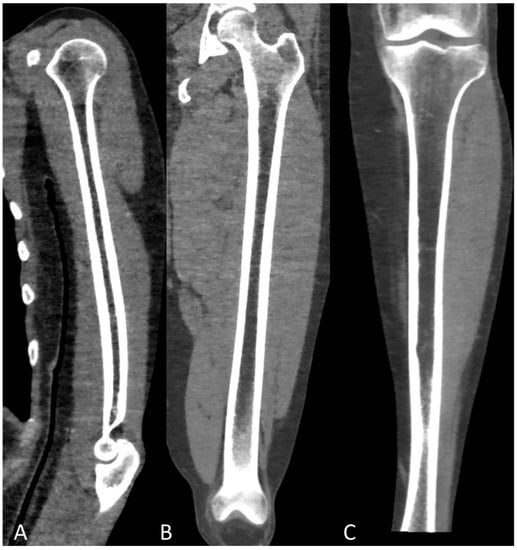

Whole-Body Low-Dose Multidetector-Row CT in Multiple Myeloma: Guidance in Performing, Observing, and Interpreting the Imaging Findings

3. WBLD-CT Imaging Findings and Evaluation